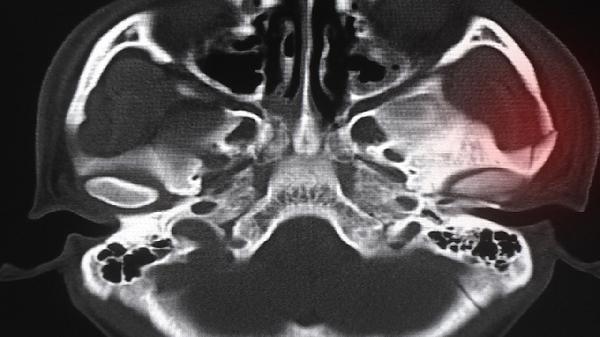

萎缩性鼻炎手术多少钱 不同手术方式萎缩性鼻炎不同

回答: 萎缩性鼻炎手术一般需要5000-30000元,具体费用与手术方式、病情严重程度及地区经济水平相关。 萎缩性鼻炎手术费用差异主要取决于术式选择。黏膜下填充术采用自体脂肪或硅胶等材料...